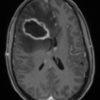

Apxe não

» Thông tin: Nam giới – 35 tuổi.

» Lâm sàng: Đau đầu.